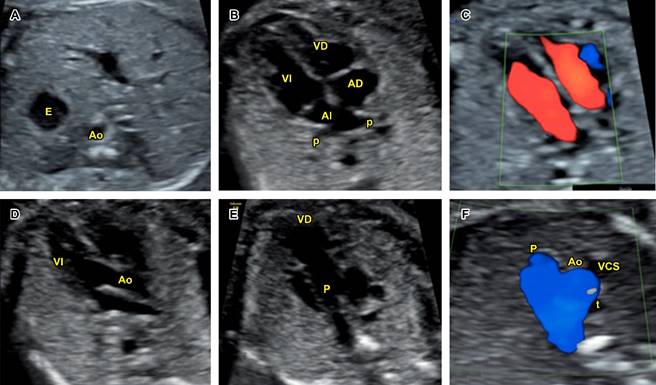

Figura 2: Evaluación cardiaca fetal básica en segundo y tercer trimestre: A) corte de abdomen superior; B) corte de cuatro cámaras; C) corte de cuatro cámaras con Doppler color; D) tracto de salida del ventrículo izquierdo; E) tracto de salida del ventrículo derecho; F) corte de tres vasos y tráquea con Doppler color.

Se realiza como parte de la evaluación anatómica fetal de segundo trimestre, entre la semana 18 y 24.3,4,7,8,10 Inicia con la evaluación de la presentación y posición fetales, determinando como referencias el lado derecho e izquierdo del feto. Incluye los cinco planos axiales descritos por Yagel, e idealmente se complementa con Doppler color (Figura 2).4,7-10 Los aspectos a evaluar (lista de cotejo) se resumen en la Tabla 2. Esta evaluación permite identificar 82% de cardiopatías congénitas.11